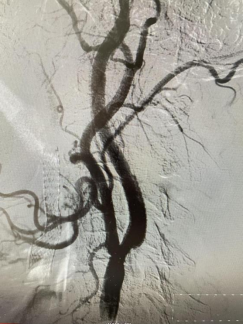

(右側(cè)頸內(nèi)動脈治療后) (左側(cè)頸內(nèi)動脈治療后)

患者是一位古稀老人,已飽受高血壓病困擾,1月前行頭頸血管檢查可見雙側(cè)頸內(nèi)動脈狹窄80%以上,其發(fā)生中風(fēng)風(fēng)險極高?;颊呒覍僬业缴窠?jīng)內(nèi)科尋求進一步診治。因為患者高齡,雙側(cè)頸動脈嚴重狹窄,無頸動脈內(nèi)膜剝脫術(shù)(CEA)指征,科室團隊討論后決定為其行頸動脈支架植入術(shù)(CAS)。對于介入治療,該患者也面臨同期或分期完成雙側(cè)頸動脈支架植入治療的選擇。分期雙側(cè)頸動脈支架植入有增加病人痛苦、住院時間長和費用增加的缺點,以及術(shù)中、術(shù)后低灌注引起未治療側(cè)腦梗死,術(shù)后高灌注造成治療側(cè)腦出血等風(fēng)險。同期雙側(cè)頸動脈支架植入術(shù)增加手術(shù)操作的時間和難度,雙側(cè)頸動脈狹窄同時解除會使顱內(nèi)血流迅速增加,與分期手術(shù)相比,可能會增加潛在的高灌注綜合征發(fā)生的風(fēng)險,同時刺激雙側(cè)頸動脈竇壓力感受器,可能會導(dǎo)致更嚴重、持久的血流動力抑制,甚至心跳驟停。通過與家屬積極溝通,科室團隊充分討論后,決定采用同期雙側(cè)頸內(nèi)動脈支架植入術(shù)治療方案??剖覉F隊完善術(shù)前準備,制定各項手術(shù)應(yīng)急預(yù)案和措施,手術(shù)順利。術(shù)后科室團隊密切監(jiān)護患者生命體征,無神經(jīng)功能缺損癥狀出現(xiàn),現(xiàn)患者痊愈出院。